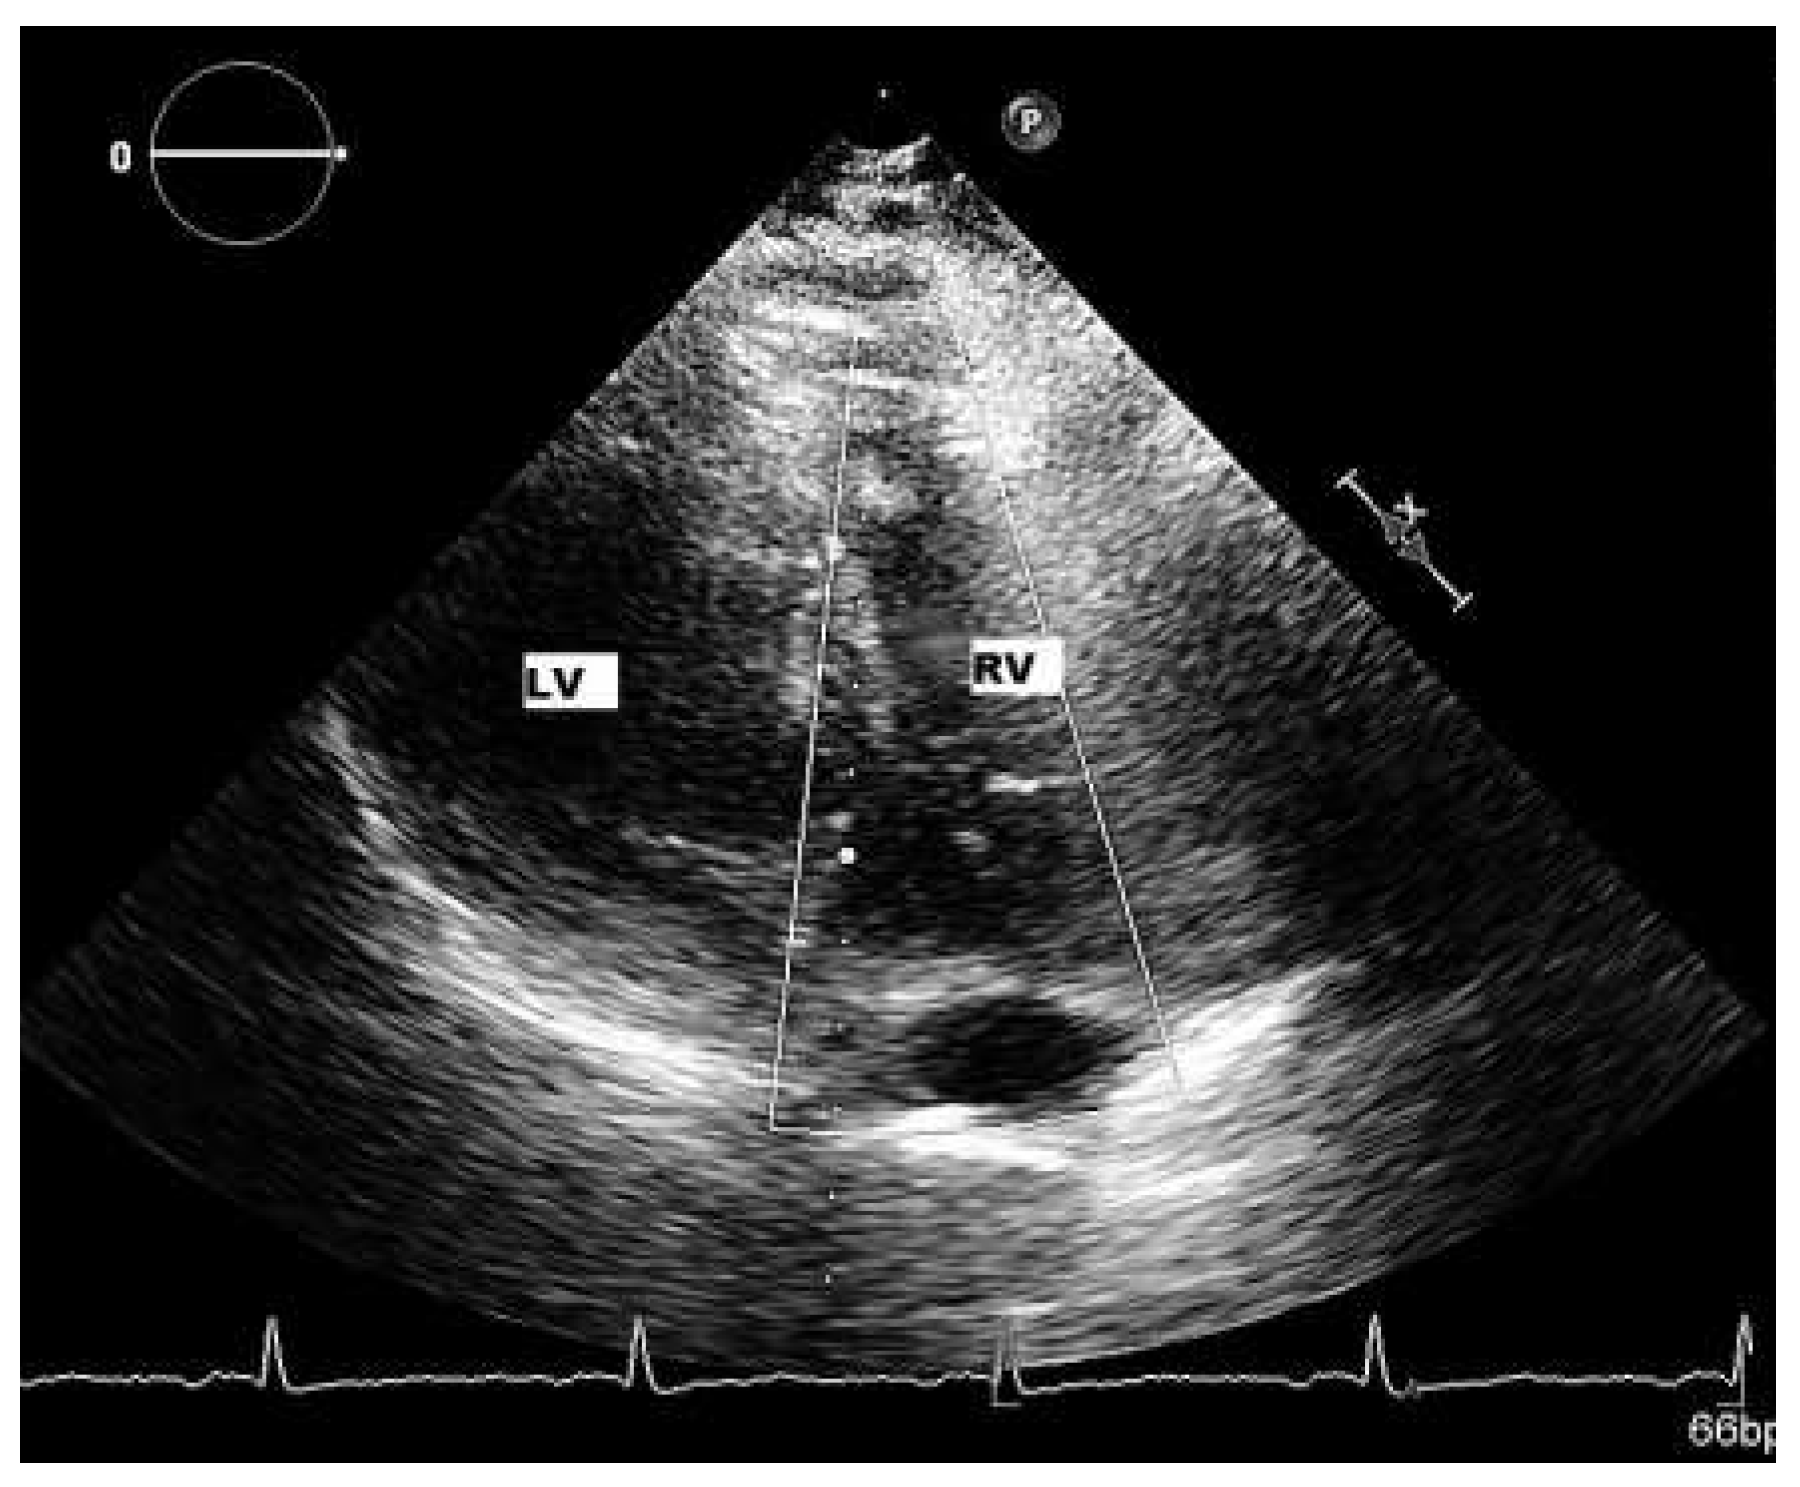

Patient